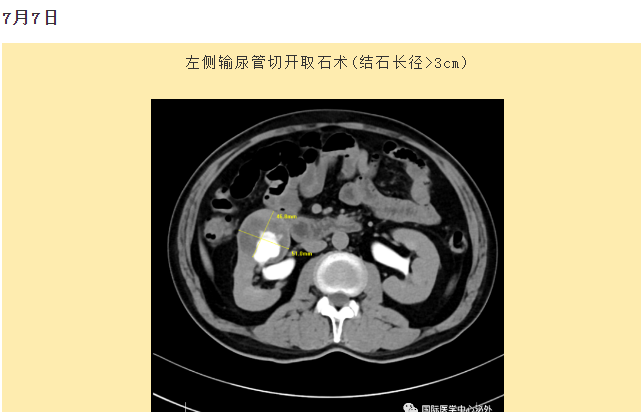

西安國際醫(yī)學(xué)中心醫(yī)院順利完成了達芬奇Xi(第四代)機器人裝機。7月6日—7月15日,泌尿外科成功完成了達芬奇Xi(第四代)機器人手術(shù)6例,標志著科室微創(chuàng)外科邁入新時代,造福萬千患者。